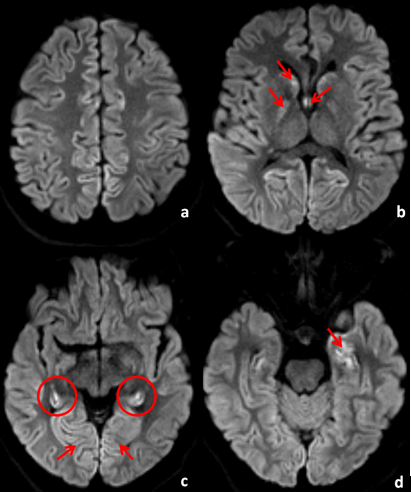

The CT scan was followed by a brain MRI 3 days later which showed restricted diffusion on DWI involving the caudate nuclei, globus pallidus and the forniceal columns ([Figure 2]a). There was also restricted diffusion and cortical hyperintensity seen in bilateral hippocampi ([Figure 2]b) as well as within the left amygdala ([Figure 2]c).